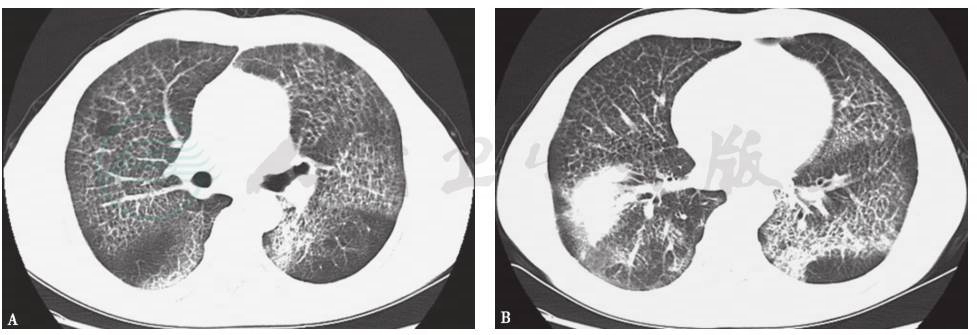

胸部CT:双肺可见弥漫性网格状密度增高影,支气管壁增厚;右下肺可见团片状密度增高影,边缘不清,密度不均,有小空洞形成;双侧胸膜肥厚粘连,气管、支气管通畅,纵隔淋巴结增大(图1)。

图1 入院第2天胸部CT表现

胸部CT可见双肺弥漫性网格状密度增高影(A),右下肺团片状密度增高影(B)